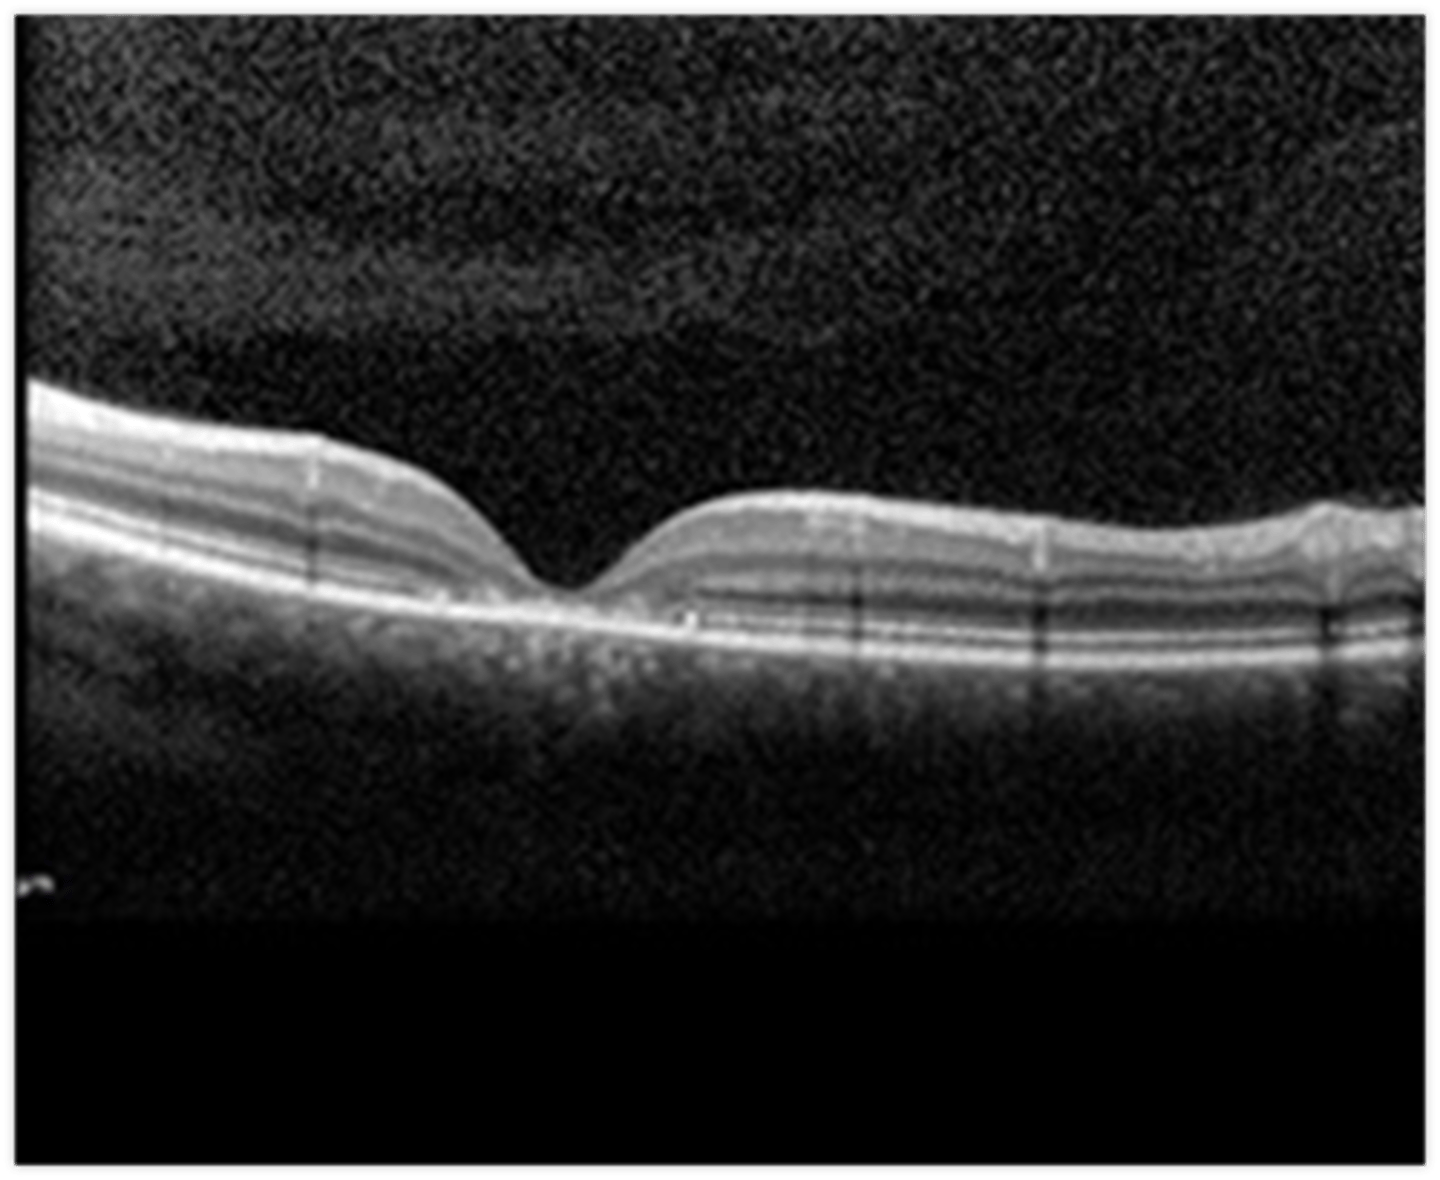

How does RP appear on OCT?

cystic macular lesions, ERM, VMT in some RP pt's with reduced central VA - may have outer>inner retinal layer thinning

What feature of RP sine pigmento is seen here?

perifoveal loss of PR's and RPE on OCT = ring scotoma very close to fixation seen on HVF

What feature of sectoral RP is seen here?

still has PIL loss and RPE thinning on OCT